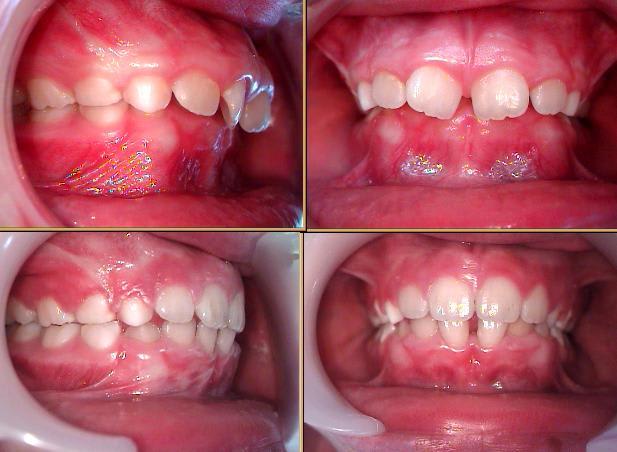

Deuxième exemple, avec une photo récente, puisque cas déja présenté sur eugénol.

Là ce qui est interessant, c'est de voir l'espace d'inocclusion au niveau des dents de lait.

En effet, il y avait une usure importante des dents de lait. Ce qui est considéré comme normal par Planas, du fait d'un bon fonctionnement des latéralité.

En dentosophie, on va trouver cela pathologique, signe d'un problème : notre petit patient se bouffe lui-même, fonctionne sur un schéma de destruction, qui ne peut que s'agraver au fil du temps.

Le traitement par activateur lui a permis de sortir de ce schéma, et de reprendre une croissance verticale interrompue, tout du moins diminuée.

Sb encombrement levé de supra fqhy3h - Eugenol

Un autre exemple : Jeune fille de 9 ans et demi. traitement commencé en janvier, revue hier. Uniquement en activateur.

Exemple supra sb vafkci - Eugenol